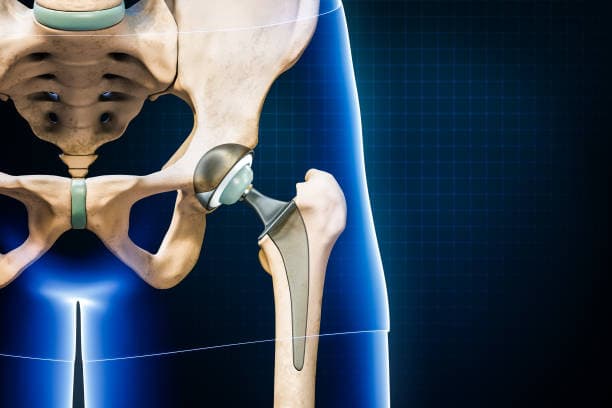

The surgical procedure involves making an incision over the hip, through which the surgeon accesses the joint. The damaged femoral head is removed and replaced with a metal or ceramic ball attached to a stem that fits into the femur. The acetabulum is also prepared by removing any damaged cartilage and bone, then resurfaced with a metal or plastic cup. These prosthetic components are designed to mimic the natural anatomy and movement of the hip joint, allowing for smooth articulation and reduced pain.

Implant Placement: The prepared bone surfaces are fitted with the prosthetic components. The femoral component, which includes a metal stem and a ball, is inserted into the femur. This can be cemented in place or designed to allow bone growth into the implant. The acetabular component, typically a metal shell with a plastic or ceramic liner, is placed into the prepared socket. These components are aligned to ensure proper joint movement and stability.